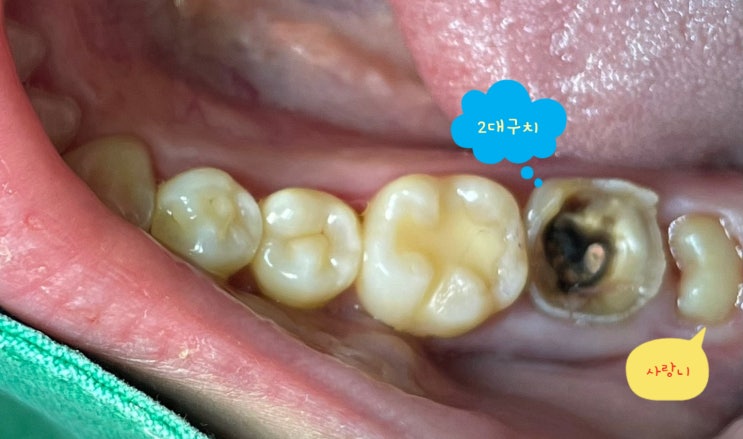

뿌리까지 충치 먹은 자연치아를 포스트 크라운으로 살려쓰기

여기저기 문제가 많지만 특히 오래전 씌운 하악우측 구치 2개를 뽑고 임플란트를 하라는 진단을 받은 분입...